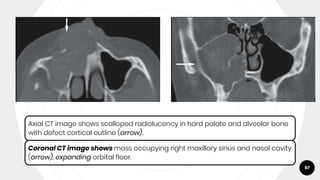

Axial CT image shows scalloped radiolucency in hard palate and alveolar bone

with defect cortical outline (arrow).

Coronal CT image shows mass occupying right maxillary sinus and nasal cavity

(arrow), expanding orbital floor.